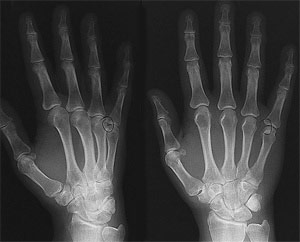

Radiography is the use of x-ray radiation to produce 2-dimensional images of internal body structures to help physicians diagnose and treat various medical conditions.

X-ray imaging is painless and has been in use since 1895. Medical uses of x-ray are many, ranging from imaging the skeletal system of bones, to imaging soft tissues such as lungs with chest x-rays, or intestinal or urinary system structures with contrast materials.

- X-ray assists doctors in the identification and treatment of a broad range of conditions, including fractures, arthritis, joint injuries, etc.